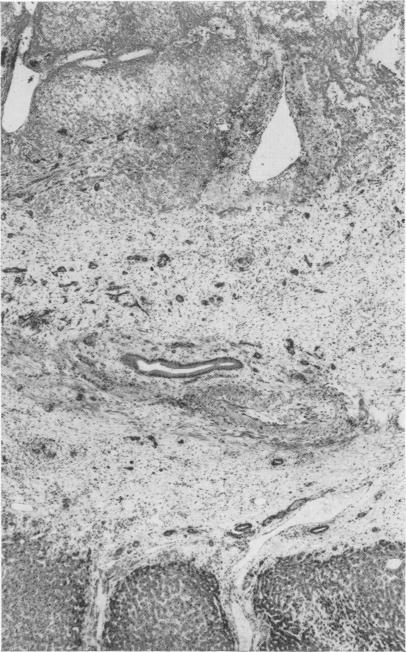

Ischemia potentiating cryosurgery of primate liver.

Ann Surg. 1971 Aug;174(2):309-18. doi: 10.1097/00000658-197108000-00019.